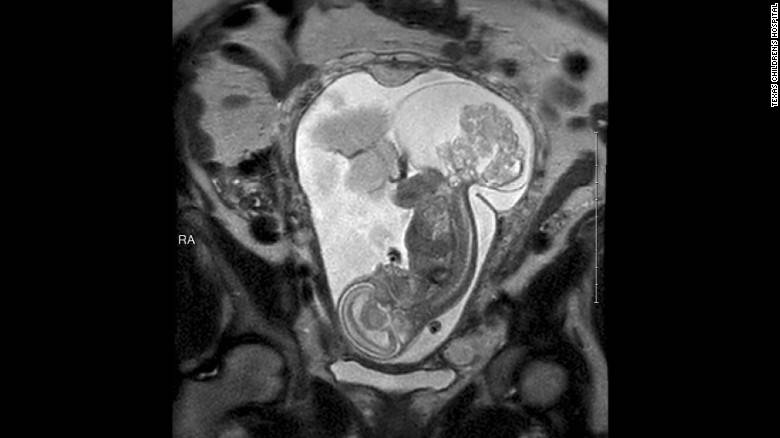

Un teratoma sacro-coccigeo o del retto è un tumore dei tessuti embrionali nella parte finale della colonna vertebrale

A 23 settimane e 5 giorni Cass ha effettuato l’operazione chirurgica fetale, e il tumore era grande quasi quanto il feto. L’operazione è durata circa 5 ore, anche se la parte effettuata sul feto è durata solo 20 minuti. La maggior parte del tempo è stato impegnato nell’aprire l’utero e nel richiuderlo in maniera da renderlo meglio sigillato possibile.

Il dottor Cass ha poi raccontato che poiché il tumore era veramente grande, l’incisione dell’utero è stata forzatamente grande, e il bambino era praticamente fuori, mentre il liquido amniotico è drammaticamente fuoriuscito. Durante l’operazione il cuore di LynLee ha avuto un bassissimo battito, quasi si è fermato.